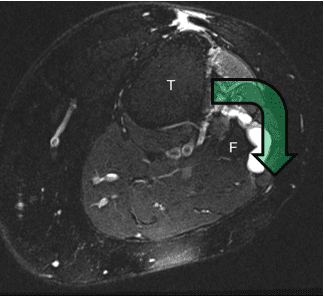

De cyste ontstaat bij het gewricht tussen het scheenbeen (tibia, T) en het kuitbeen (fibula, F), het zogenoemde tibiofibulaire gewricht. Vanuit dit gewricht loopt een klein zenuwtakje naar de hoofdzenuw (nervus peroneus). Via dit kleine takje kan de cyste in de hoofdzenuw terechtkomen. Dat kan pijn veroorzaken en in sommige gevallen zelfs leiden tot uitval van de zenuw.

Toen men nog niet wist hoe dit precies ontstond, werd alleen de cyste in de hoofdzenuw behandeld. Tegenwoordig richt de behandeling zich op de oorzaak. Daarbij wordt de verbinding via het kleine zenuwtakje afgesloten door het takje af te binden en door te nemen.